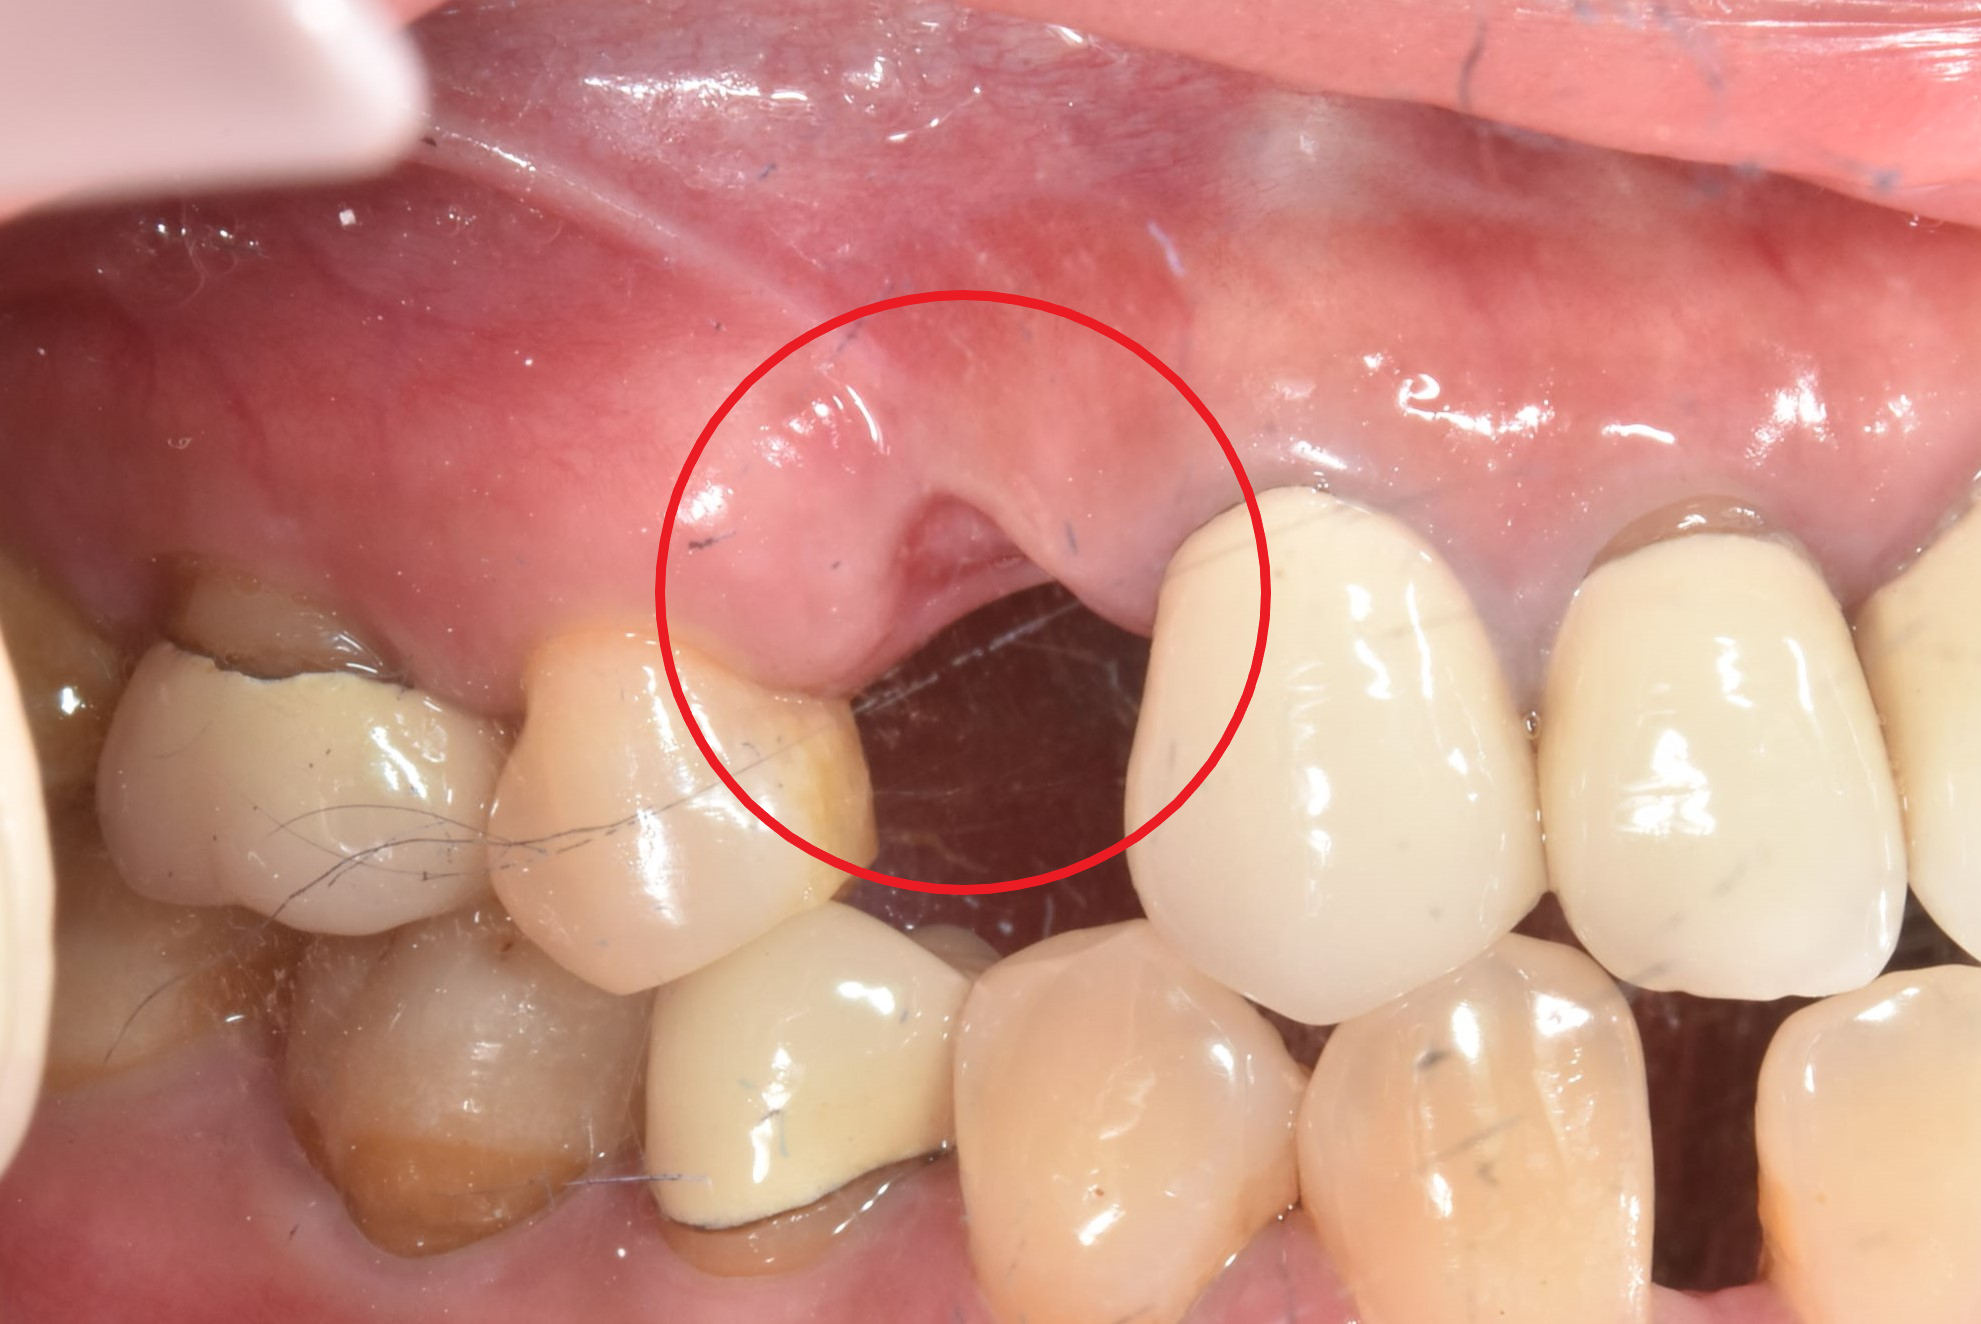

骨頭明顯凹陷